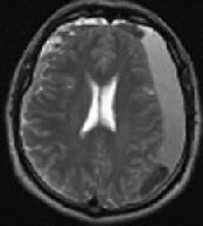

![САК-обр]()

МРТ головного мозга. Аксиальная МРТ типа FLAIR. Аневризма и САК, внутрижелудочковое кровоизлияние.

Субарахноидальное кровоизлияние опасно вазоспазмом, который наблюдается на 5-7 сутки. Сам спазм хорошо определяется при дуплексном сканировании. При МРТ головного мозга можно выявить ранние признаки ишемического инсульта.